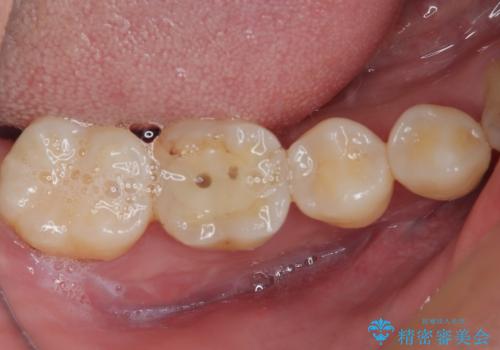

- 他院で矯正治療前後に処置を行った歯が痛むとのことで来院された患者様です。

下顎大臼歯は根管治療がされている歯が咬合時に痛みを感じ、上顎の大臼歯2歯は冷たいものがしみる状態でした。

まずはしみる上顎の歯を仮歯に置き換え、その後下顎の根管治療を行った上で、異常が認められなければオールセラミッククラウンにて補綴治療を行うこととしました。